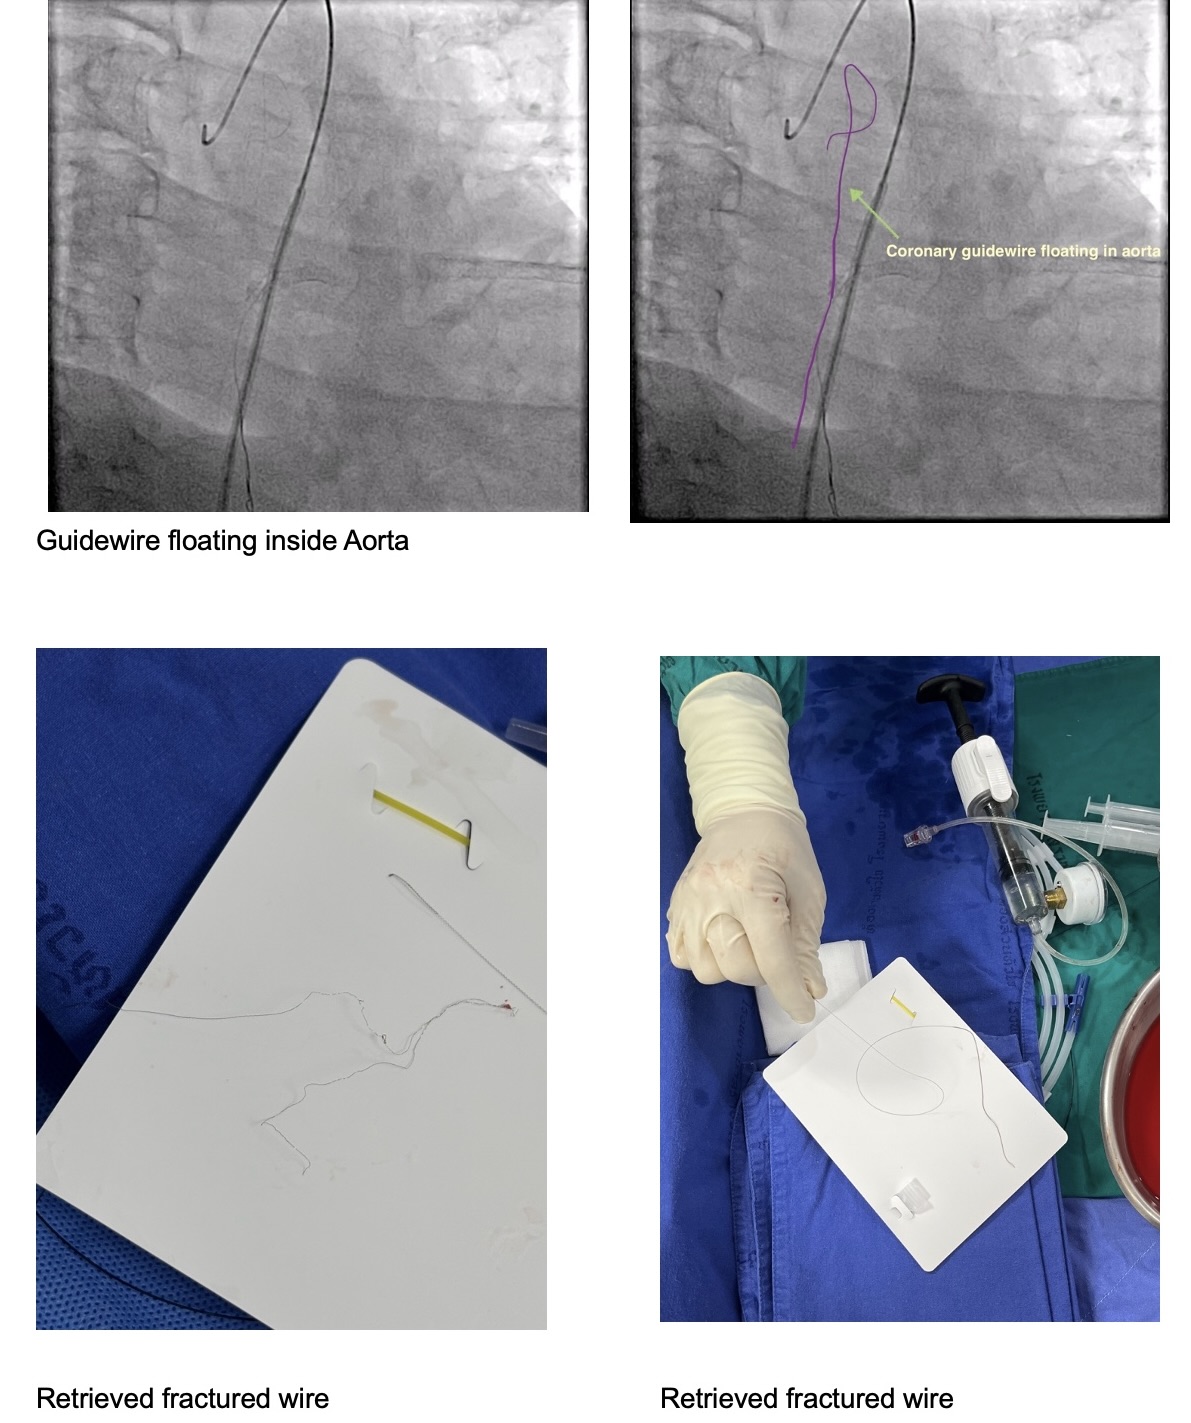

Microcatheter (Finecross) with Fielder XT to RCA, unable to pass the CTO lesion then changed to Gaia 2nd which was unsuccessful too and finally changed to Gaia 3rd. Gaia 3 rd guidewire got stuck at distal RCA. Snare catheter 8 mm was inserted to retrieve Gaia 3rd guidewire which was unsuccessful (Several attempts). Turntrac guidewire and Fielder-XT was inserted across the lesion to twist wire for Gaia 3rd retrieval, but failed and complete fracture of all three wires happened. Snare Size 8 mm was inserted for retrieval but failed.Smaller snare size 7 mm and 4 mm were inserted for retrieval but failed.Left femoral artery puncture with 8 Fr. Sheath. Guiding catheter JR 4.0/7 was used. Snare 8 mm and 15 mm via LFA could retrieve some part of wire. Decided to leave the wire at RCA due to several failed attempts. Angiogram was done before stopping the procedure. As we were removing the catheter, thin stretched guidewires were seen floating in the ascending aorta till descending aorta. Snare 15 mm could remove the wire floating in the aorta after several attempts.Final angiogram showed retained some parts of fractured guidewires and planned to leave it there. The patient was asymptomatic and hemodynamically stable.

1. Factors that predispose to guidewire fracture include severe vessel calcification, sharp side branch angulation, excessive wire manipulation, and variations in wire length or thickness 2. Guidewire is thrombogenic and its presence inside the coronary or hanging up into the aorta may carry a risk of thrombo-embolization, making its removal essential. 3. Strategies for retrieval of fractured guidewire includes snaring, multiwire technique, trapping techniques, stenting, surgical removal or leaving the corpus alienum in-situ. 4. GooseNeck snare is a feasible approach for retrieving a lost guidewire confined to proximal coronary artery.